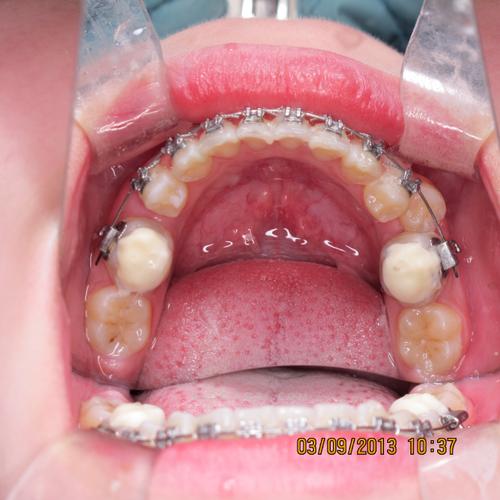

开窗牵引(针对完全埋伏尖牙)

- 外科暴露与粘接附件:在局部麻醉下,沿尖牙牙冠位置切开牙龈,去除部分牙槽骨,暴露牙冠表面;彻底清理牙面,酸蚀后粘接正畸附件(如托槽或牵引钩),避免损伤牙髓(若尖牙牙根发育未完成,需注意保护牙乳头)。

- 安装牵引装置:选择合适的支抗(如微种植体植入上颌颧牙槽嵴或下颌骨体部),用镍钛拉簧或弹性链连接牵引钩与支抗体,施加50-100g的轻力(避免过大力量导致牙根吸收)。

- 加力与调整:每4-6周复诊一次,检查牵引效果,调整牵引力方向(必要时更换牵引钩角度),确保尖牙沿牙长轴移动,避免倾斜。